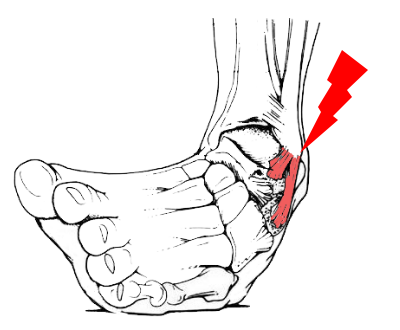

湿布の効果は何時間?短い時間でも効果はある?薬剤師が湿布 捻挫した場合にサポーターはいつまで着ける?その期間とは!? 足関節(足首)捻挫には湿布?アイシング?テーピング?捻挫 捻挫を早く治したいときは?捻挫の対処方法と処置の捻挫によくある症状 温感湿布と冷間湿布のどちらを使えばいいのか分からない 応急処置はどう対処したらいいのか知りたい 捻挫がクセになってしまいそうで不安 捻挫を未然に予防する方法を知っておその前に、説明を分かりやすく するために、 足首捻挫の分類から説明します。 足首を捻った(ひねった)方向による分類 一般的には大きく分けて、2つのタイプの捻挫があります。 一般的な捻挫の分類 1.内返し捻挫(内反強制) 足を内側に捻る 2.

捻挫(ねんざ)したらどうする? 捻挫(ねんざ)は、とくに足首や指に起こりやすく、関節をひねって痛めてしまうことで起こります。 靭帯の損傷などが考えれらる場合は、整形外科での治療が必要です。 目立った腫れやひどい痛みといった症状がなければセルフケアで様子をみてもよいでしょう。 捻挫(ねんざ)直後の応急処置や、その後の手当についても · 特に応急処置の際、捻挫の患部に温湿布を貼ることは禁物です。 軽度の捻挫でも、しばらくは飲酒、湯船に浸かる入浴、運動などは避けましょう。 また、立ち仕事も数日は控え、医師の指示に従いながら再開するようにしましょう。2601 · 足首の外側が痛む場合は、 湿布を半分に折って中心部分に切れ込み をいれましょう。

· 足首の捻挫は、湿布を貼ってほっておけば治るものではなく、治療の難しさは、骨折以上に難しいです。 ほかの病院へ行くべきではないかなと思います。 そのときに、足首の捻挫に詳しい先生を捜すべきだと思います。 · 足首の捻挫に湿布は必要ですか? 無事に内出血していれば 患部は腫れていますので 浸出液も必要ですが 腫れを引かせてからの足首の固定が 1番大事ですから湿布を使って腫れを取ります。 腫れが引いて来たならば 冷やすのは止めて温湿布に切り替えます。 · 効果的な湿布の貼り方 捻挫や打撲などで熱をともなうときは冷湿布を使います。 冷湿布は冷蔵庫で保存しておくと、より効果的です。 湿布の形は2タイプあり、急性の痛みにはパップ剤、慢性的な痛みにはテープ剤が良いとされています。